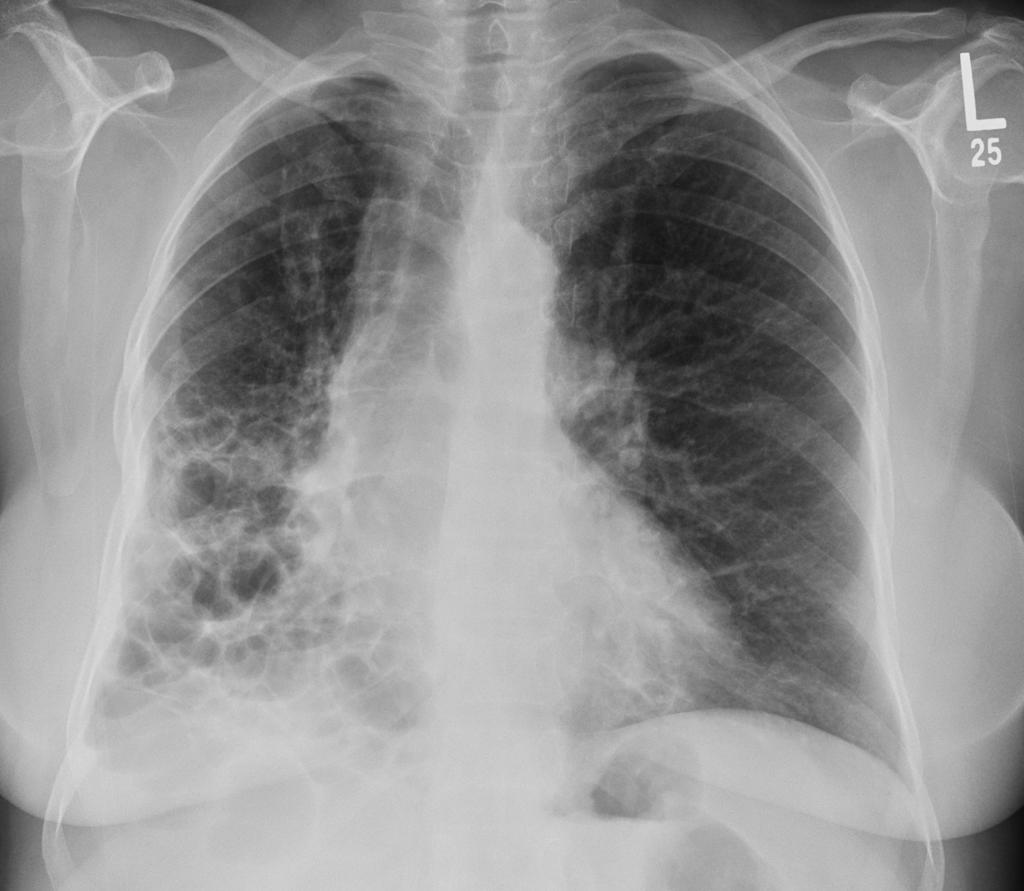

间质性肺疾病的病理生理机制

间质性肺疾病的疾病概述与定义

提到肺病,大多数人想到的可能是肺炎、肺癌这些"知名度"比较高的疾病,但有一类肺病却像个"隐形杀手",悄悄地损害着我们的肺部,它就是间质性肺疾病,简称ILD。 ...